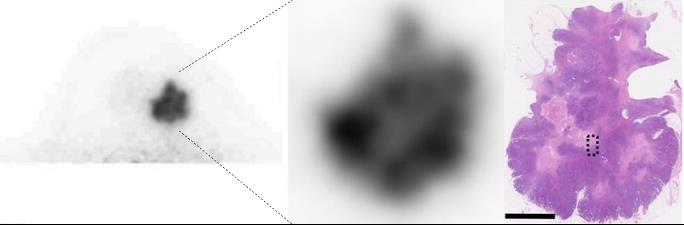

We proceed with development and clinical application of new modalities of breast imaging; portable microwave breast tumor detector and ring-type dedicated breast PET.

Microwave breast imaging (left) and visualization of intratumoral heterogeneity using dedicated breast PET.